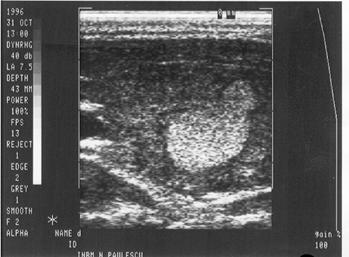

Spatiul fizic de separare dintre structuri sau tesuturi cu densitati diferite (respectiv impedante acustice diferite) se numeste interfata. Interfata este cu atat mai evidenta cu cat diferenta dintre densitatea tisulara este mai mare. De exemplu, limita de separatie intre chiste si tesuturile solide invecinate este foarte evidenta; de aceea chisturile din interiorul unui parenchim sunt vizibile ecografic chiar la dimensiuni mici. Foto I 62 (chist).

Cu cat diferenta dintre densitatea tesuturilor este mai mica, cu atat interfata dintre acestea apare mai putin distinct pe ecranul ecografului. De exemplu, un nodul parenchimatos cu densitate identica cu aceea ce inaparent ecografic chiar la dimensiuni mari. Fig 83 b, pag. 72 Badea.